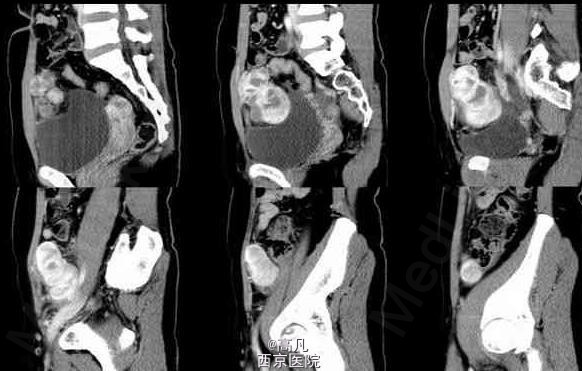

患者有周期性尿频、尿痛、血尿 辅查CT:右下腹可见囊实性不规则形肿块,实性为主。增强扫描不规则增厚的囊壁,内有多个大小不等囊变坏死区。